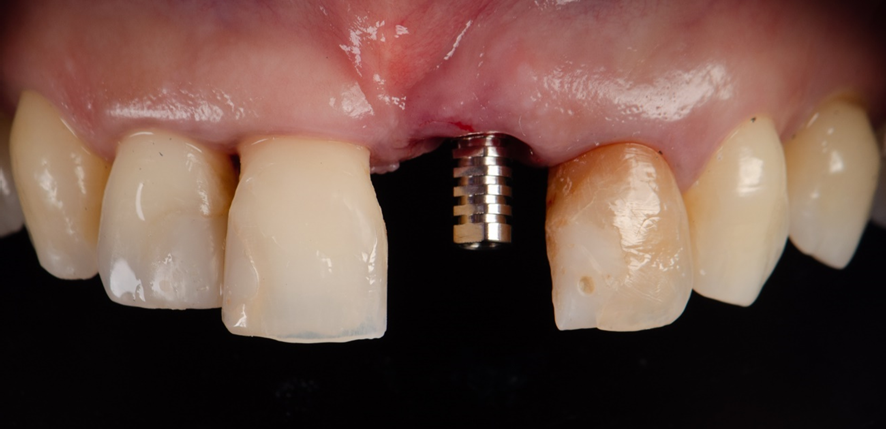

Após o implante instalado, a guia é então removida, e um SmartPeg é fixado sobre a plataforma do implante.

O Osstell é então posicionado sobre o SmartPeg, e os valores de ISQ foram obtidos atraves da RFA, sendo 64 no sentido Vestibulo-Palatino e 65 no sentido Mesio-distal. Isso fez com que optássemos por um cicatrizador personallizado, potencializando assim, um resultado mais previsível.

Foi então feito uma ROG (Extra Graft®) na região de GAP entre o implante e o osso alveolar, e confeccionado um cicatrizador personalizado sobre um pilar provisório, para manutenção do arcabouço gengival.

Pilar provisório posicionado.